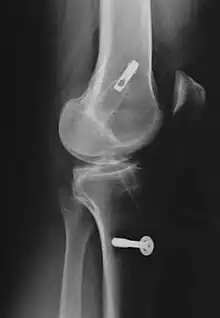

![]() | |

| Arthroscopic anterior cruciate ligament (ACL) reconstruction (right knee). The tendon of the semitendinosus muscle was prelevated, folded and used as an autograft (1). It appears through the remnant of the injured original ACL (3). The autograft then courses upwardly and backwardly in front of the posterior cruciate ligament (2). | |